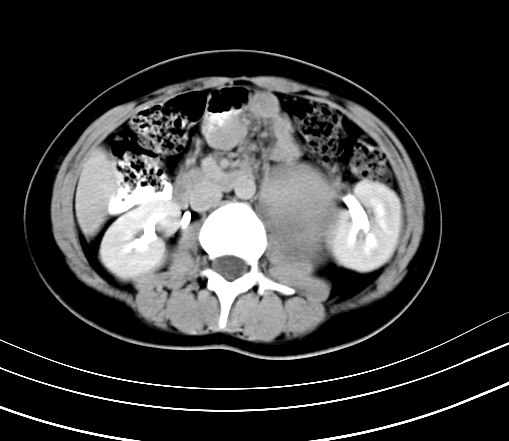

腹部平扫